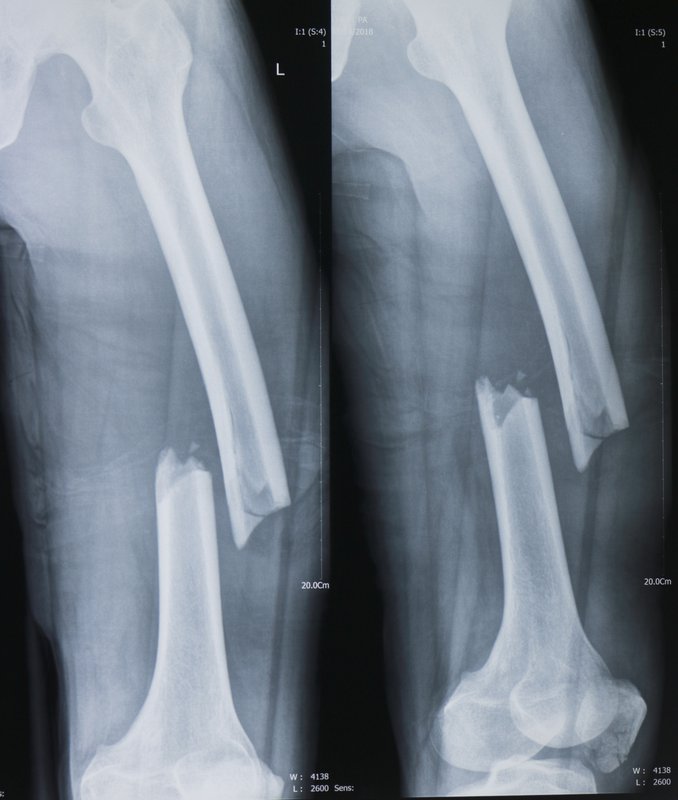

Gãy xương đùi hay gãy thân xương đùi là một tổn thương nghiêm trọng xảy ra khi cấu trúc xương đùi bị phá vỡ do tác động của ngoại lực. Tình trạng này không chỉ gây đau đớn mà còn làm hạn chế đáng kể khả năng vận động ở các khớp như háng và gối, từ đó làm ảnh hưởng nghiêm trọng đến chất lượng cuộc sống của người bệnh.

Tùy thuộc vào lực tác động, xương đùi có thể bị gãy theo nhiều cách khác nhau. Các mảnh xương vỡ có thể bị xê dịch hoặc vẫn đúng vị trí và chỗ xương bị gãy có thể kín (da còn nguyên vẹn) hoặc hở (xương đâm xuyên da).

• Vị trí gãy xương (được phân loại thành ba đoạn chính trên thân xương đùi: xa, giữa và gần).

• Các kiểu gãy xương (ví dụ: xương có thể bị gãy ở nhiều hướng khác nhau như gãy ngang, gãy dọc, gãy chéo, gãy nhiều mảnh, gãy 2 hoặc 3 đoạn)

Gãy thân xương đùi ở người lớn sẽ điều trị theo phương pháp phẫu thuật.